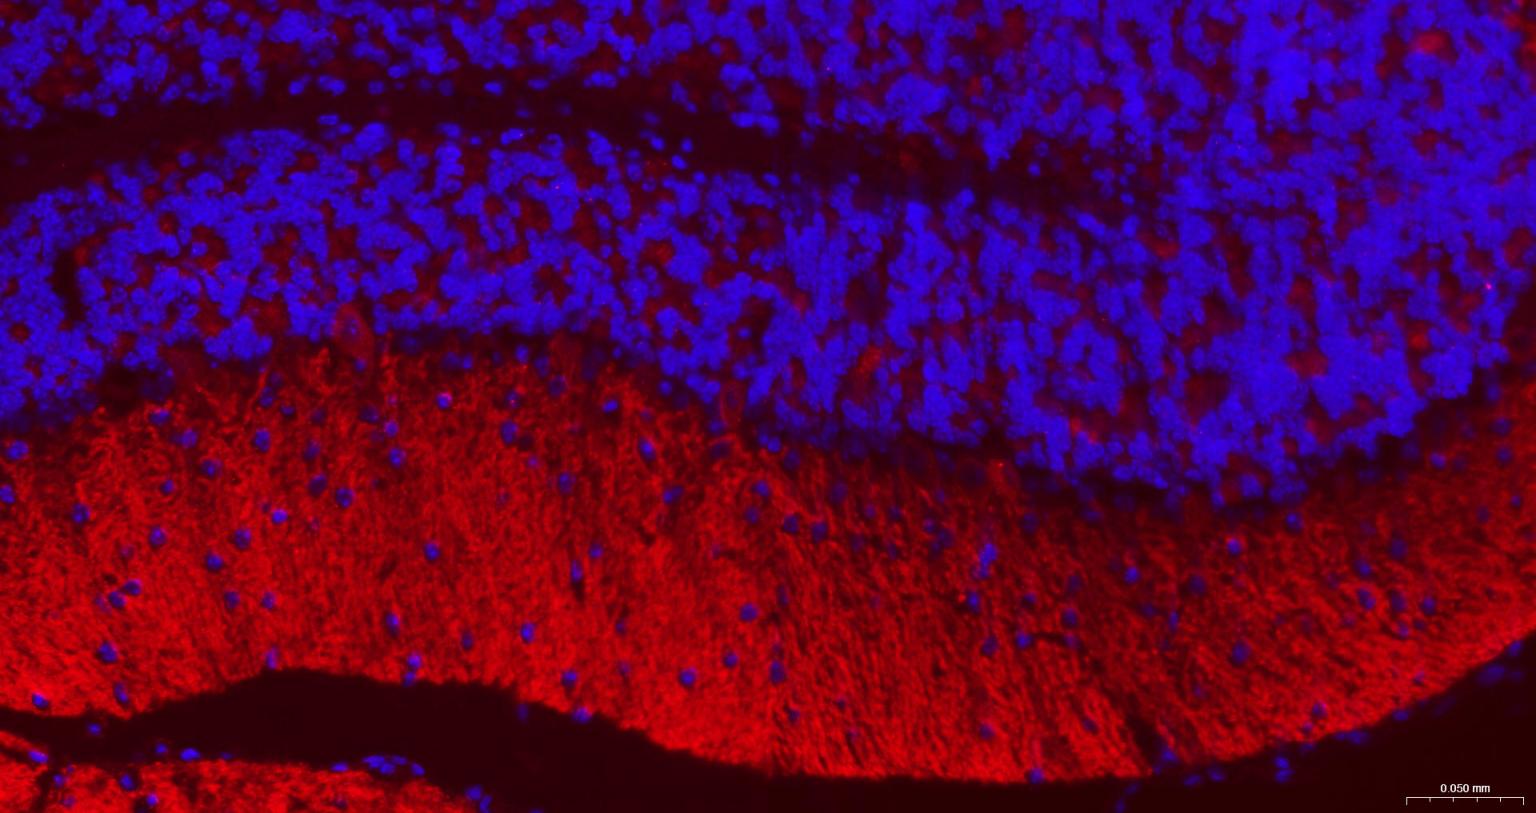

Paraformaldehyde-fixed, paraffin embedded Mouse Cerebellum; Antigen retrieval by boiling in sodium citrate buffer (pH6.0) for 15 min; The section was incubated with GABBR2 Monoclonal Antibody, Unconjugated (bsm-54237R) at 1:200 overnight at 4°C. Followed by conjugated Goat Anti-Rabbit IgG antibody (Red, bs-0295G-BF594), DAPI (blue, C02-04002) was used to stain the cell nuclei.